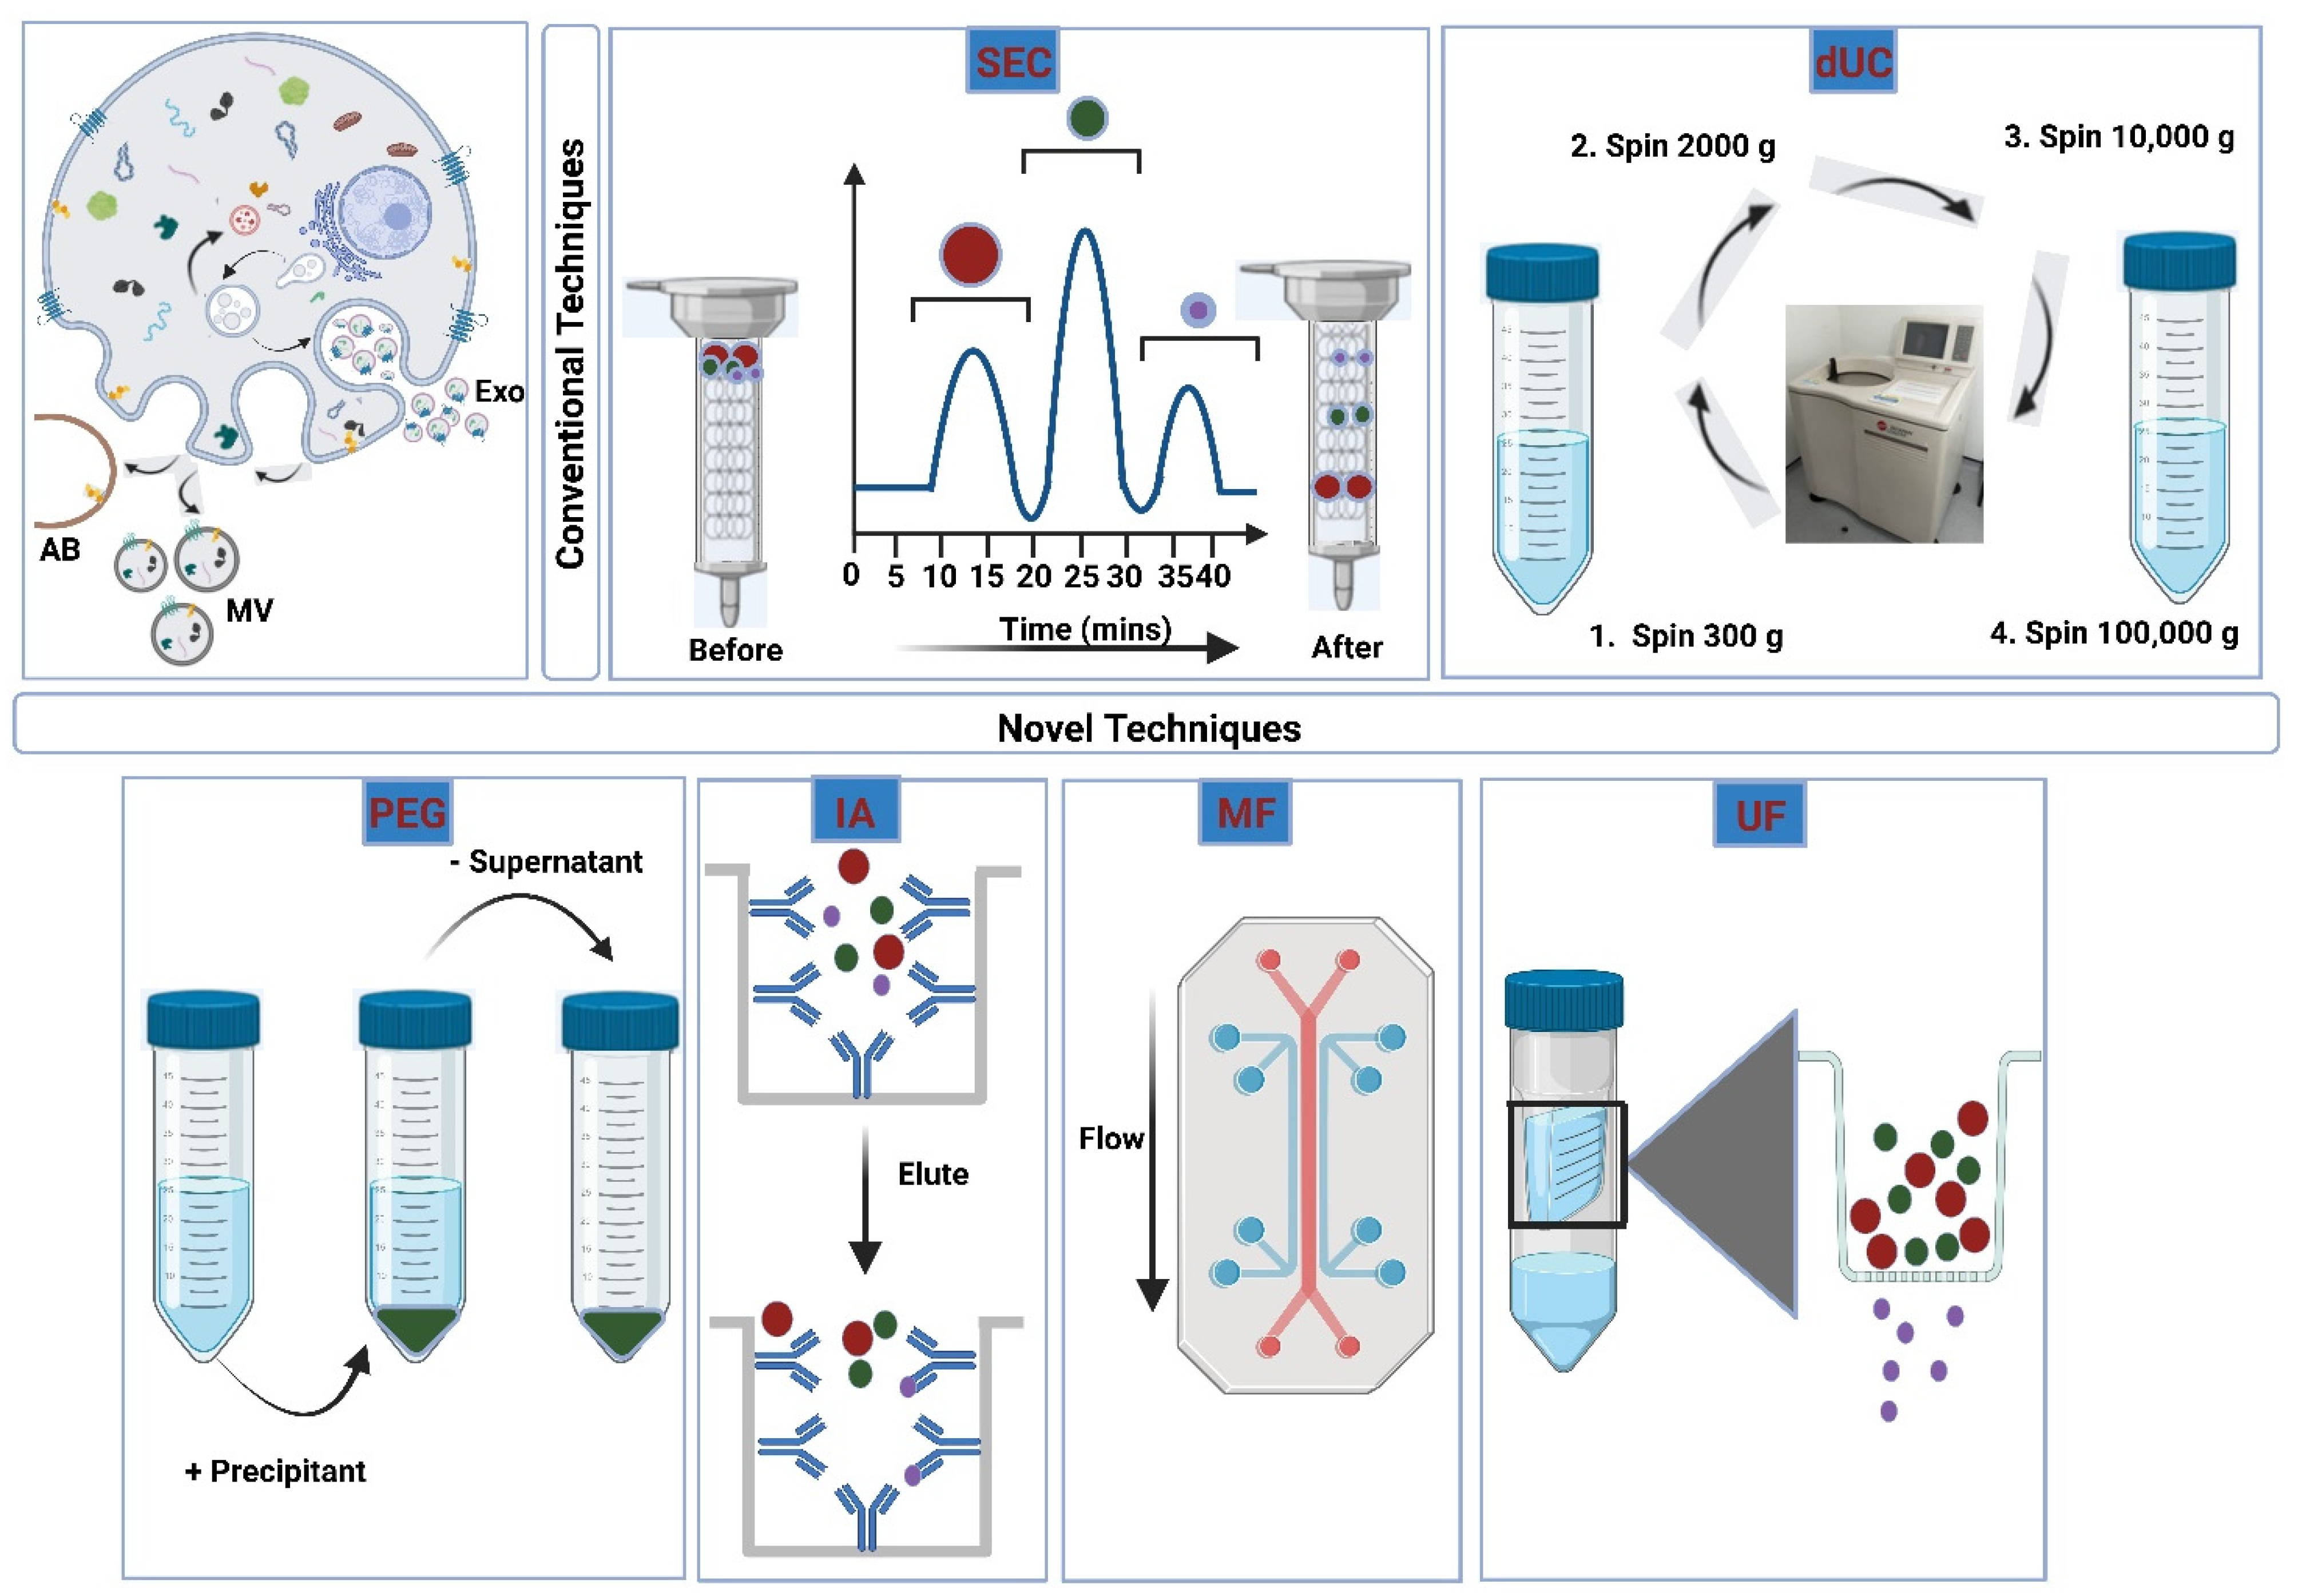

3.2. Isolation of Extracellular Vesicles

3.2.1. Ultracentrifugation

3.2.2. Size-Exclusion Chromatography

3.2.3. Ultrafiltration

3.2.4. Polymeric Precipitation

3.2.5. Immunoaffinity Isolation

3.2.6. Microfluidic Devices